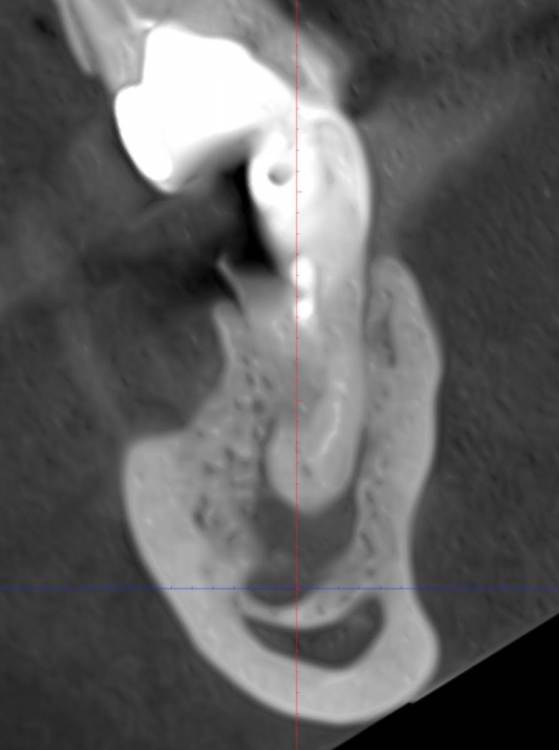

safroxa Опубликовано 7 марта, 2023 Автор Поделиться Опубликовано 7 марта, 2023 Здравствуйте уважаемые доктора. Лечу зубы. Дошла до нижней семёрки справа. Ситуация такая: канал проходит слишком близко к нерву. Доктор посоветовал удалить и поставить имплант. Есть ли шанс, все же залечить каналы и спасти зуб? Ссылка на комментарий

safroxa Опубликовано 17 марта, 2023 Автор Поделиться Опубликовано 17 марта, 2023 Еще раз здравствуйте, дорогие доктора. Обратилась с вопросом о нижней семерке справа к другому врачу. Сказал, что попробует помочь, но гарантий нет. На днях залечила 6-ку (рядом), врач сказал, что на него необходима тоже коронка. Скажите пожалуйста, если не удастся спасти 7-ку, нужен ли будет имплант на его место или достаточно коронки на 6-ке? Снимок еще раз прилагаю. Хорошего ортопеда в нашем городе найти сложно. Ссылка на комментарий

Doc Опубликовано 17 марта, 2023 Поделиться Опубликовано 17 марта, 2023 Есть шансы у этого зуба или нет, сказать может только тот врач, который возьмется. Чаще всего есть, но далеко не всегда. Если удалить и не протезировать, то верхняя семерка со временем, скорее всего, начнет сдвигаться в низ и блокировать движение нижней челюсти. Это не очень хорошо. Так что лучше поставить имплантат, тем более, что кость там вполне хорошая. 1 Ссылка на комментарий